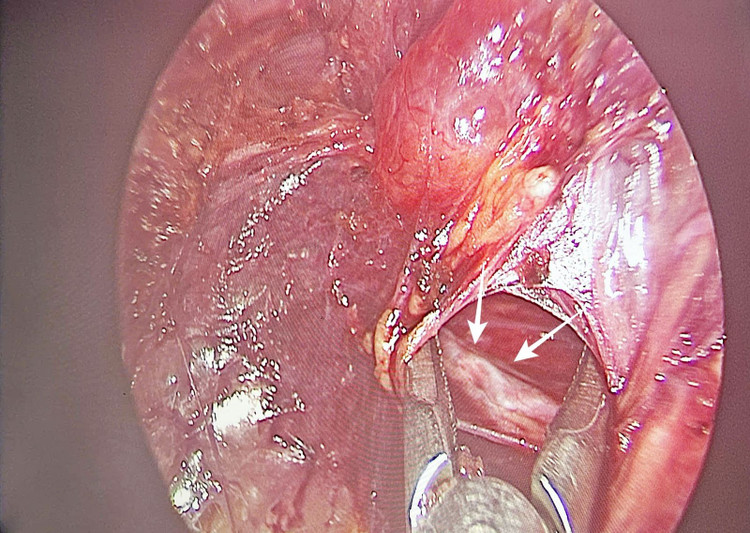

Qua 3 đường rạch nhỏ ở môi trước trong khoang miệng, phẫu thuật viên thực hiện bóc tách lớp dưới cơ bám da cổ để đưa dụng cụ nội soi vào tuyến giáp theo đường giữa, kíp mổ khéo léo phẫu tích cắt thùy trái chứa khối ung thư và eo tuyến giáp, nạo vét hạch cổ, bảo tồn dây kinh thần kinh thanh quản quặt ngược và tuyến cận giáp.

Hình ảnh phẫu tích cắt thùy trái chứa khối ung thư và eo tuyến giáp, nạo vét hạch cổ, bảo tồn dây kinh thần kinh quặt ngược - Ảnh BVCC